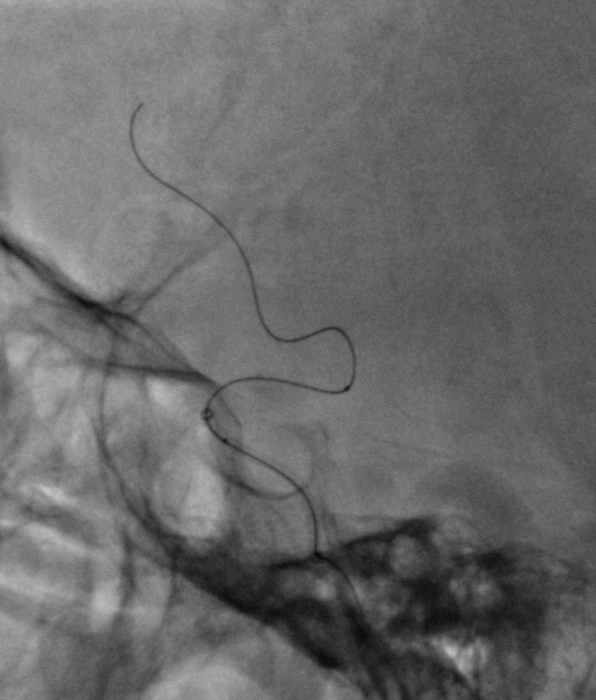

引入4.0×39mm支架,支架释放后由于张力后退。

无法回收支架,完全释放。

支架中部再狭窄明显,导丝成袢确认位于支架内并引入加奇2.25×12mm SacSpeed®球囊扩张导管。

加奇2.25×12mm SacSpeed®球囊到位并扩张。

后扩后复查造影。